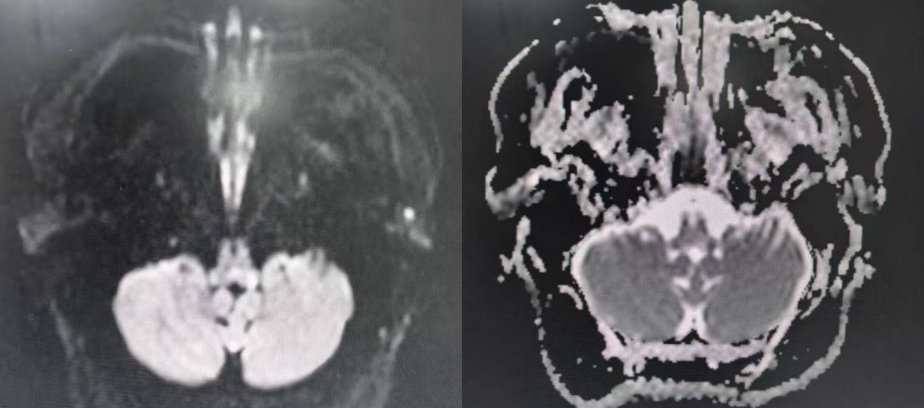

辅助检查:头部MRI:

头颅MR平扫+增强:

刘超团队的柳光林主治医师立刻为患者完善针对性检查与检验。头颅MR平扫+增强扫描结果显示:左侧延髓背侧见小片状长T1及长T2信号,弥散像未见信号明显增强,增强后无强化。结合临床考虑炎症。